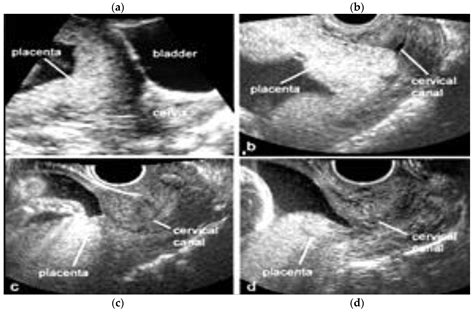

Prenatal care for COVID-19-positive mothers should be enhanced to monitor both maternal and fetal health closely. This may include:

• Frequent ultrasound examinations to assess fetal growth and development.

• Regular monitoring of maternal vital signs and symptoms.

• Close collaboration with a multidisciplinary team, including obstetricians, neonatologists, and infectious disease specialists.